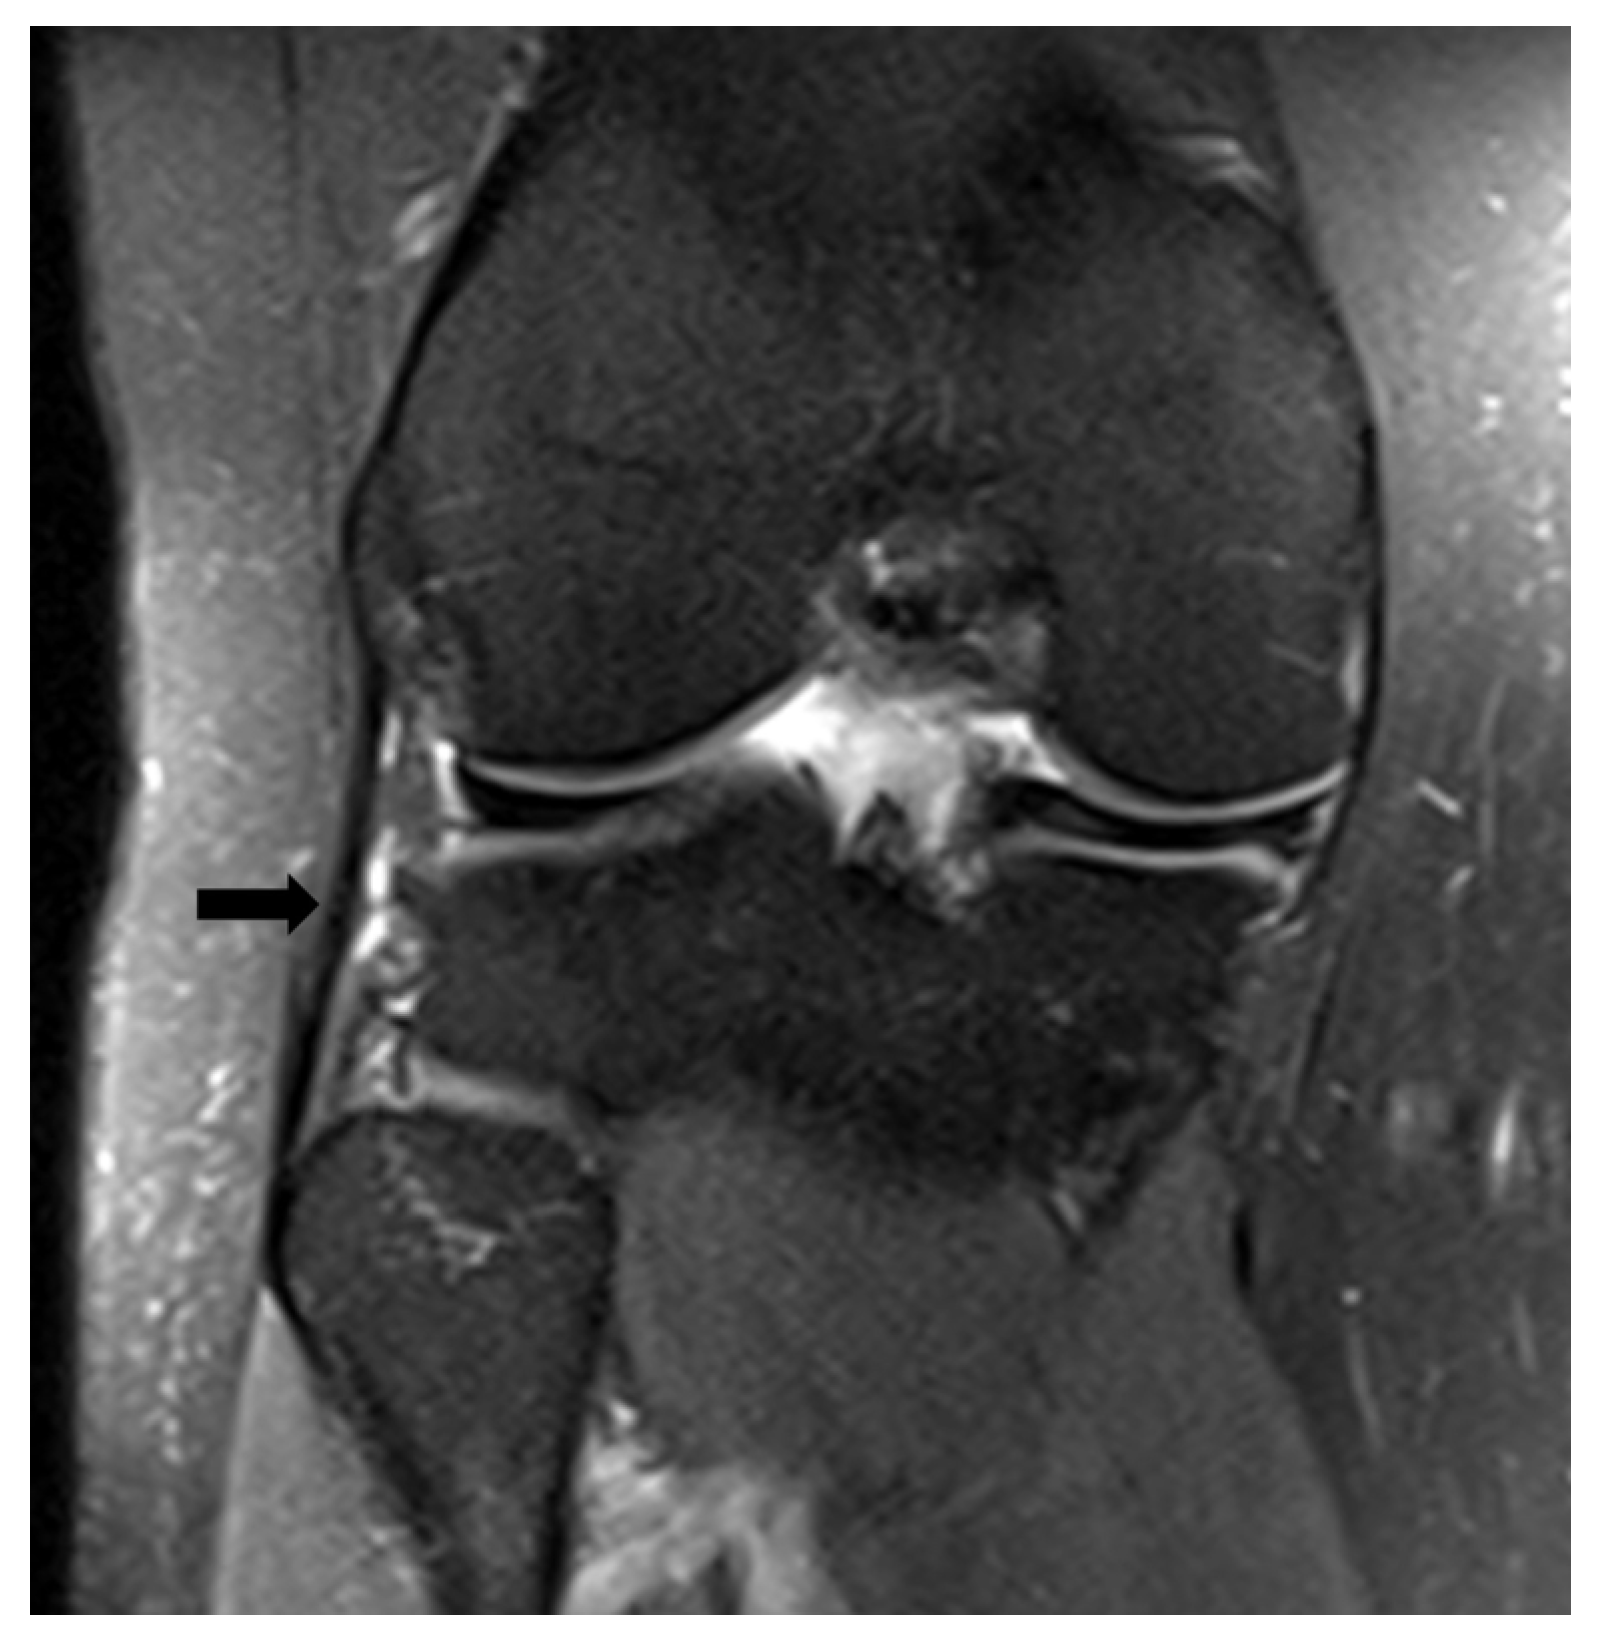

- Mitchell, B.C.; Siow, M.Y.; Bastrom, T.; Bomar, J.D.; Pennock, A.T.; Parvaresh, K.; Edmonds, E.W. Coronal Lateral Collateral Ligament Sign: A Novel Magnetic Resonance Imaging Sign for Identifying Anterior Cruciate Ligament–Deficient Knees in Adolescents and Summarizing the Extent of Anterior Tibial Translation and Femorotibial Internal Rotation. Am. J. Sports Med. 2021, 49, 928–934. [Google Scholar] [CrossRef]

- Palle, L.; Reddy, B.; Reddy, J. Sensitivity and Specificity of Vertically Oriented Lateral Collateral Ligament as an Indirect Sign of Anterior Cruciate Ligament Tear on Magnetic Resonance Imaging. Skelet. Radiol. 2010, 39, 1123–1127. [Google Scholar] [CrossRef]

- James, S.L.J.; Connell, D.A. The Vertically Orientated Fibular Collateral Ligament: A Secondary Sign of Anterior Cruciate Ligament Rupture on Magnetic Resonance Imaging. Eur. Radiol. 2006, 16, 1854–1856. [Google Scholar] [CrossRef]